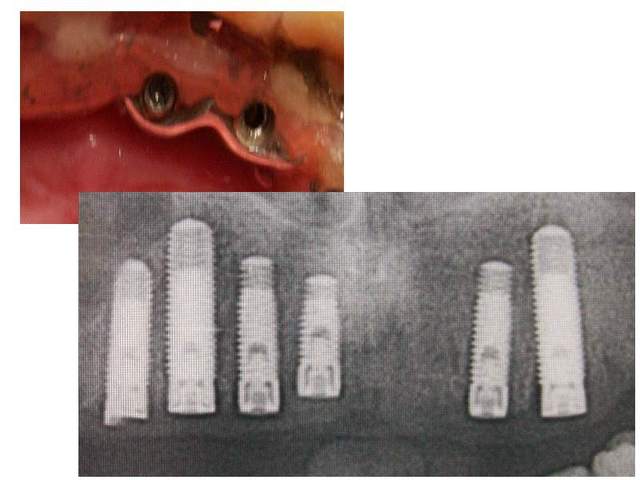

Pourriez vous me dire de quelle marque d'implant il s'agit . le confrère qui les a posé a disparu, et impossible d'avoir les renseignements nécessaires ...

+1. On dirait du screw-vent (Zimmer)...

le col parait plus fin que sur les screwvent

Merci à dentiste57 et nolive, je pense que c'est du zimmer effectivement avec ces hexagones de 1.25mmm (dommage en magasin de modélisme cela s'arrête à 1.5mm....

pendant que j'y pense...tu sembles avoir 4 implants avec plate forme 3.5... et 2 en 4.5 (diamètres implants 3.7 et 4.7)pendant que tu y est commande les transferts et analogues correspondant (après vérif...of course)chez implant direct...sont de même qualité mais beaucoup moins cher...